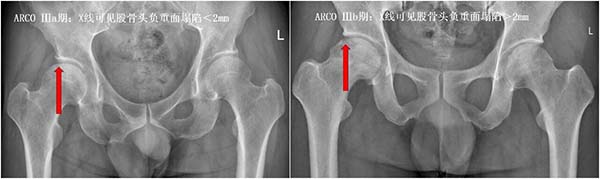

ARCO Ⅲ期:股骨头已经出现塌陷,关节功能开始受损,保髋难度明显增加,预后也会变差,部分人可能需要接受更复杂的保髋手术;

②坏死范围与位置:

除了分期,坏死的范围和位置也直接影响预后:

如果坏死范围小,且不在股骨头的“负重区”(走路、站立时承受压力的部位),股骨头不易塌陷,恢复更快,预后更好;反之,坏死范围大且位于负重区,极易出现塌陷,加重病情,预后大打折扣。